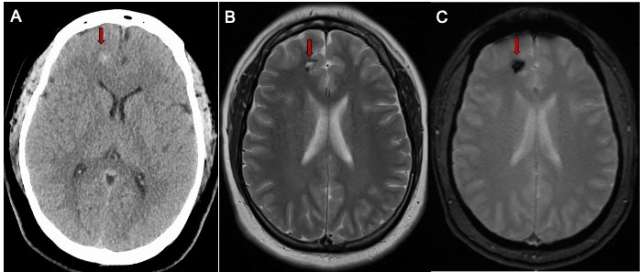

Whether the CCM has caused bleeding or not, the following advanced imaging (Figure 1) techniques may be used to diagnose it:

• Magnetic resonance imaging (MRI) scan can help locate the CCM and the area of affected brain or spinal cord.

• Computed tomography (CT) scan can assess any bleeding into the brain tissue.

Figure 1. Cerebral Cavernous Malformation Imaging - CT scan of the brain (A) in a patient with a mild headache showing a small spot of white bleeding (red arrow). B) A brain MRI scan T2 sequence demonstrating a small cavernous malformation (red arrow)